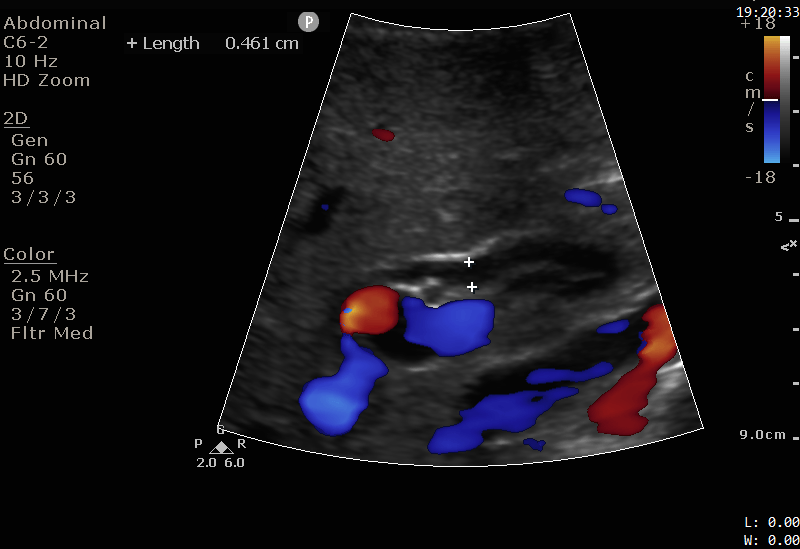

Bedside ultrasound was performed on the ward by the surgical house officer.

The images show a 1cm stone in the distal CBD. Note the hyperechoic (bright white) appearance, with a posterior acoustic shadow, similar to the appearance of gallstones discussed in Case 2. The CBD is not significantly dilated.

Images were shown to the radiologist. MRCP was avoided and the patient proceeded directly to ERCP.